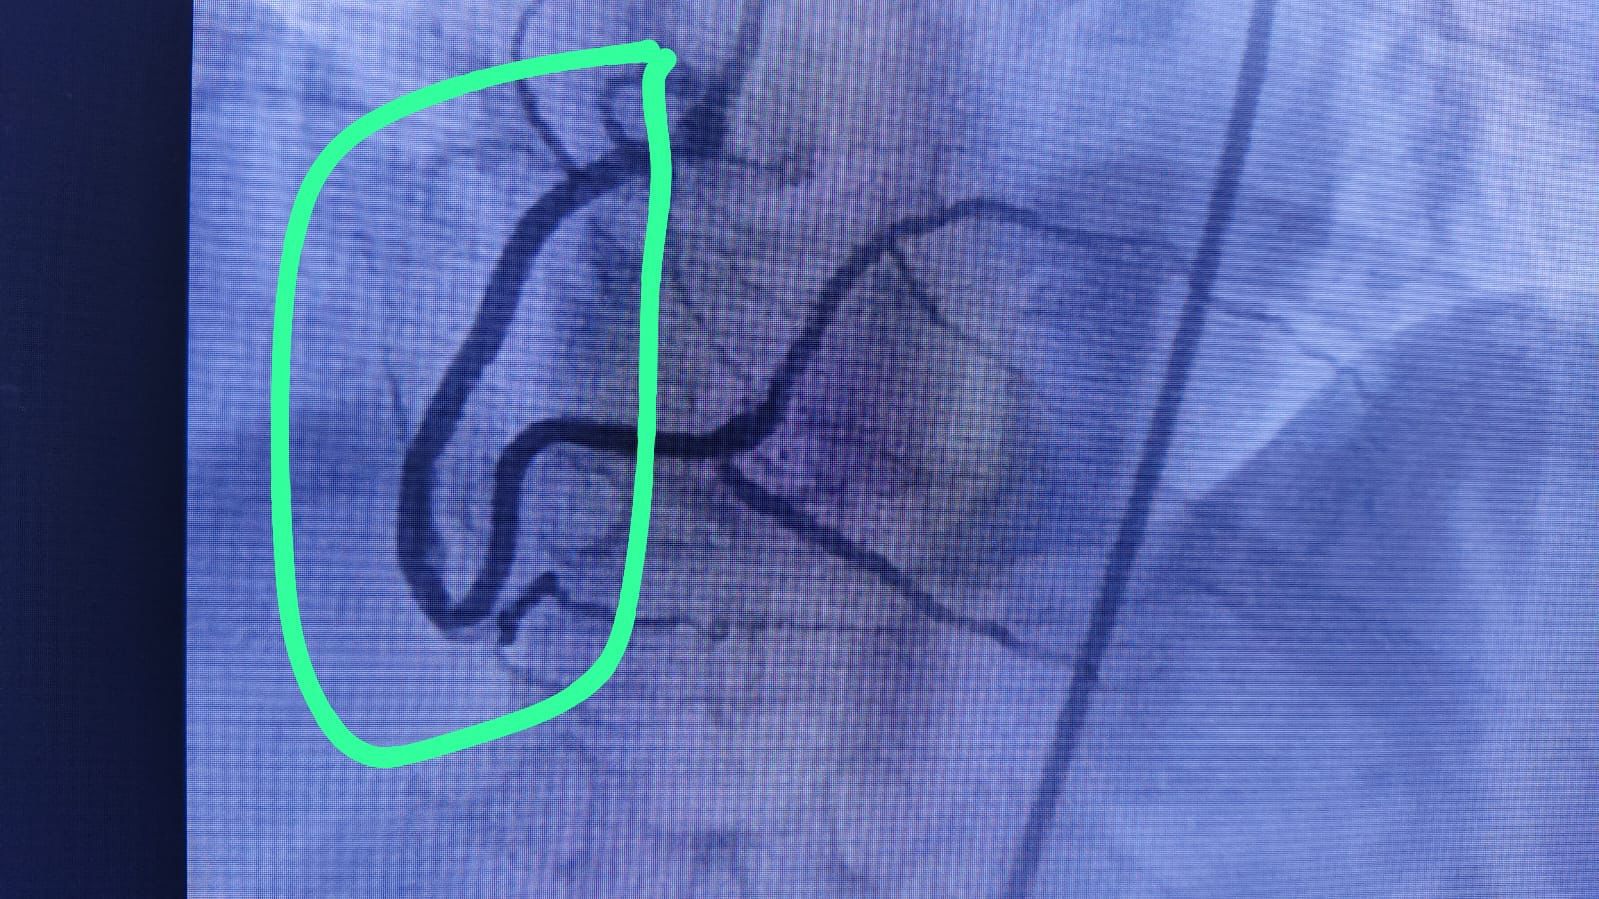

Deepa Kannan Hospital Heart Care Center & Cath Lab stands as a beacon of excellence in cardiovascular medicine. With state-of-the-art catheterization laboratory facilities and a team of renowned cardiac specialists, we are committed to providing comprehensive heart care services that combine cutting-edge technology with personalized patient care.

State-of-the-art cardiac catheterization laboratory with advanced imaging technology